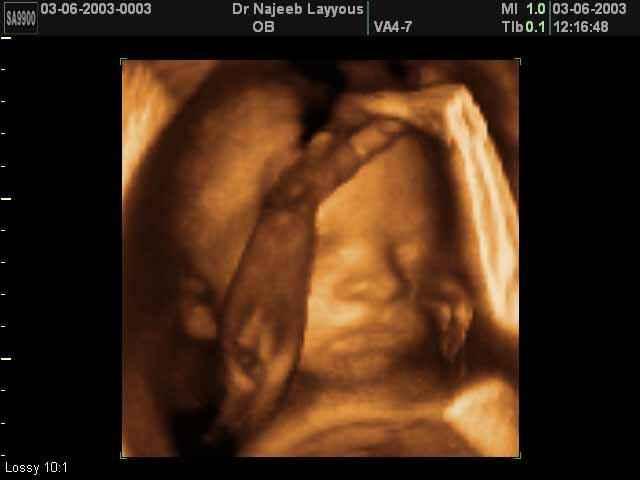

3D Fetal Face Ultrasound Scan Photos